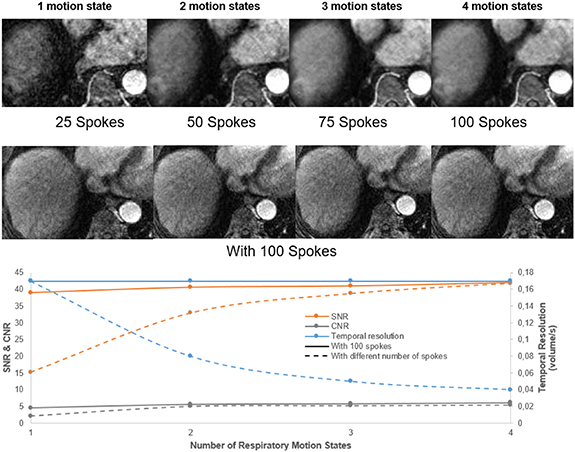

XD-GRASP reconstructed with increased motion states with different number of spokes improves the contrast-to-noise ratio and the signal-to-noise ratio (p < 0.05) but reduces temporal resolution (0.04 volume/s vs 0.17 volume/s for one motion state) (p < 0.05) (figure 6). XD-GRASP with 3 and 4 motion states had higher overall image quality scores compared to XD-GRASP with 1 and 2 motion states as it showed reduced streak artefact (figure 8). Results for image reconstructed with different number of spokes show that on average, the reconstruction with 4 phases received the higher scores (4.6) while the reconstruction with one phase received the lower one (1).

Figure 6. Example of XD-GRASP images with different number of spokes from a 70-year-old woman with HCC at 3.4 cm liver mass in segment VIII (white arrow). Its representative temporal resolution, contrast-to-noise ratio (CNR) and signal-to-noise ratio (SNR), are shown for increasing number of respiratory motion states.

Standard image High-resolution imageIn the case of XD-GRASP reconstructed with 100 spokes, there was no significant difference in SNR and CNR and the visual scoring show an average score of 4 for all cases (4, 3, 2 and 1 motion state). Since the reconstruction had a footprint of 25 spokes, the nominal temporal resolution was the same 6 s/volume while the effective one was as discussed previously.

Compared to the baseline reconstruction, we can clearly see the importance of XD-GRASP with regards to quality image as shown in figure 7. This reference reconstruction was evaluated using the same ROI and same length of time points to generate the corresponding perfusion curves and compared it to GRASP and XD-GRASP. There is a significant difference between the baseline and the images reconstructed with XD-GRASP, particularly concerning image quality, and shows higher peak of aorta concentration, but is more noisy and unstable.

Standard image High-resolution imageFigure 6 shows that increasing the number of respiratory motion states improves the SNR and CNR but reduce the temporal resolution thus influencing quantitative parameters that capture rapid signal changes. This is confirmed with figure 8, which clearly shows the improvements of the image quality by increasing the number of motion states for several patients.